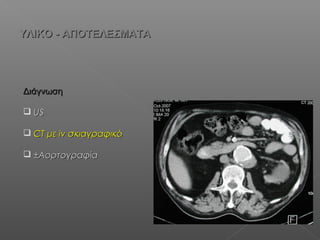

ΥΛΙΚΟ - ΑΠΟΤΕΛΕΣΜΑΤΑΥΛΙΚΟ - ΑΠΟΤΕΛΕΣΜΑΤΑ

ΔιάγνωσηΔιάγνωση

 USUS

 CTCT μεμε iviv σκιαγραφικόσκιαγραφικό

 ±±ΑορτογραφίαΑορτογραφία